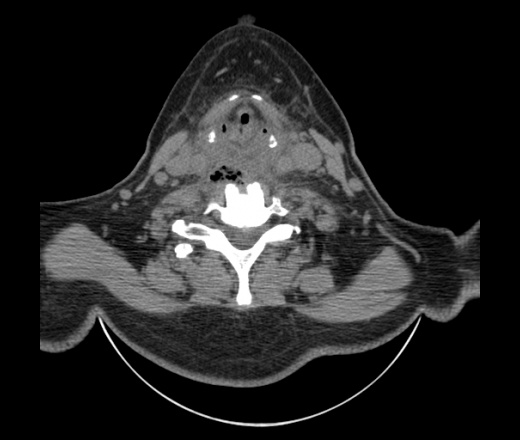

Женщина поступила в х/о спустя 4 дня после того как при употреблении карася подавилась костью.

Наличие газа в средостении на протяжении тел С2-С6 (медиастинальна эмфизема); рыбная кость на уровне тела С6.

При всем уважении, но говорить о медиастинальной эмфиземе, оценивая мягкие ткани шеи, как-то слишком резко. На мой взгляд, это ретрофарингеальное пространство.

Согласен с Вами; конечно, наличие газа в клетчатке ретрофарингеального пространства (затмение с опечаткой..). К сожалению, процесс "продвигается" к медиастиниту. Но почему никто, не отмечает наличие рыб. кости; или это для Всех очевидно?

Кость то мы сразу выявили, размеры где то 17*2мм, но ее так и не получается найти в этой каше